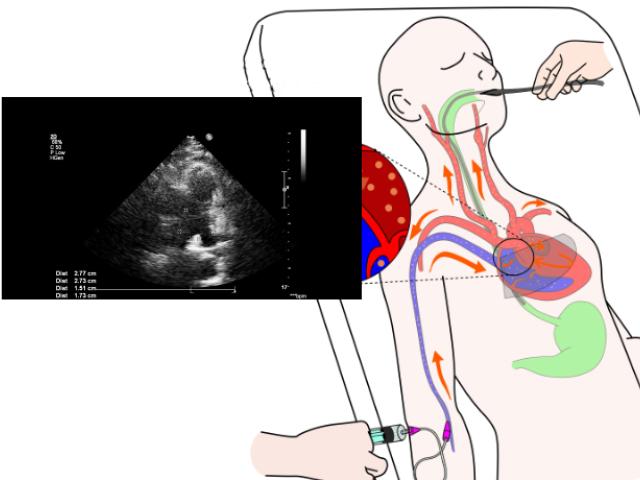

Un ecocardiograma transesofágico (ETE) es un procedimiento que utiliza el ultrasonido para producir imágenes en movimiento en tiempo real del interior del corazón.